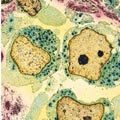

Νέα Υόρκη: Η επιβίωση των πρώτου βαθμού συγγενών με καρκίνο του μαστού προβλέπει την πιθανότητα επιβίωσης της γυναίκας, σύμφωνα με στοιχεία που δημοσιεύονται στο επιστημονικό έντυπο Breast Cancer Research.